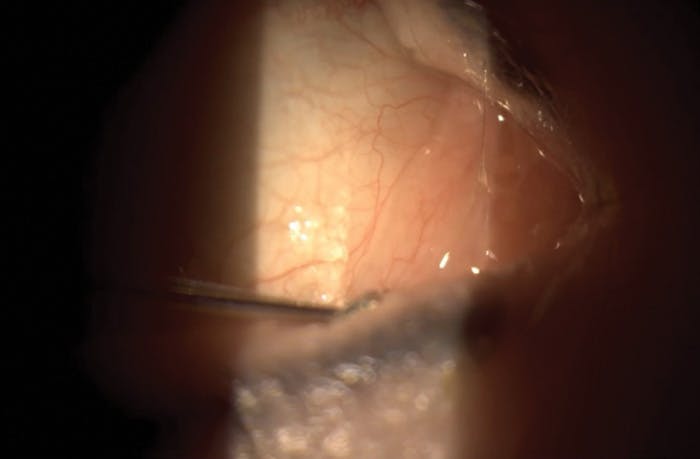

As discussed with the new diagnosis of Demodex blepharitis, I placed the patient on XDEMVY (lotilaner ophthalmic solution) twice daily for 6 weeks. This cleared her Demodex blepharitis infestation but because of this comorbidity it had exacerbated her existing DED to an uncontrollable level. At her follow-up visit in October 2024, the patient's osmolarity was still normal, but her SPEED questionnaire measured 10/28, and I found significant inferior corneal staining as well as a low tear meniscus height (TMH). It was at this visit that I instilled LACRIFILL Canalicular Gel at 0.1 mL per puncta. She has a connected canalicular system, meaning that I only had to place the cannula in the lower puncta to achieve a full fill of the lower and upper canalicular system. Clinically, the only way to know that this system is connected is by regurgitation of the gel through the upper puncta while filling the lower puncta (Figure).

<p>Figure. Instillation of LACRIFILL Canalicular Gel was determined necessary upon the patient’s follow-up visit.</p>

Figure. Instillation of LACRIFILL Canalicular Gel was determined necessary upon the patient’s follow-up visit.